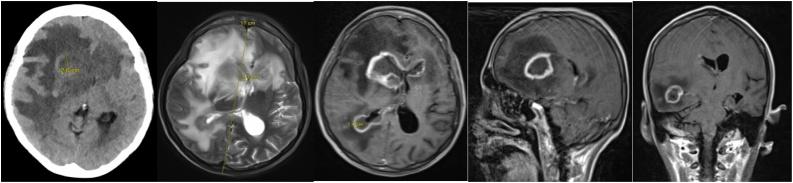

Diagnosis of primary CNS lymphoma in a HIV patient with multiple ring-enhancing lesions.

Multiple ring-enhancing lesions on brain MRI in an immunocompromised patient are frequently associated with opportunistic infections such as toxoplasmosis. In this report, we describe the case of a patient with HIV/AIDS who was found to having multiple ring-enhancing lesions and was diagnosed with a primary central nervous system lymphoma.

免疫功能低下患者脑部磁共振成像(MRI)上出现的多发环形强化病灶常与机会性感染相关,如弓形虫病。在本报告中,我们描述了一例人类免疫缺陷病毒(HIV)/获得性免疫缺陷综合征(AIDS)患者,该患者被发现有多发环形强化病灶,并被诊断为原发性中枢神经系统淋巴瘤。